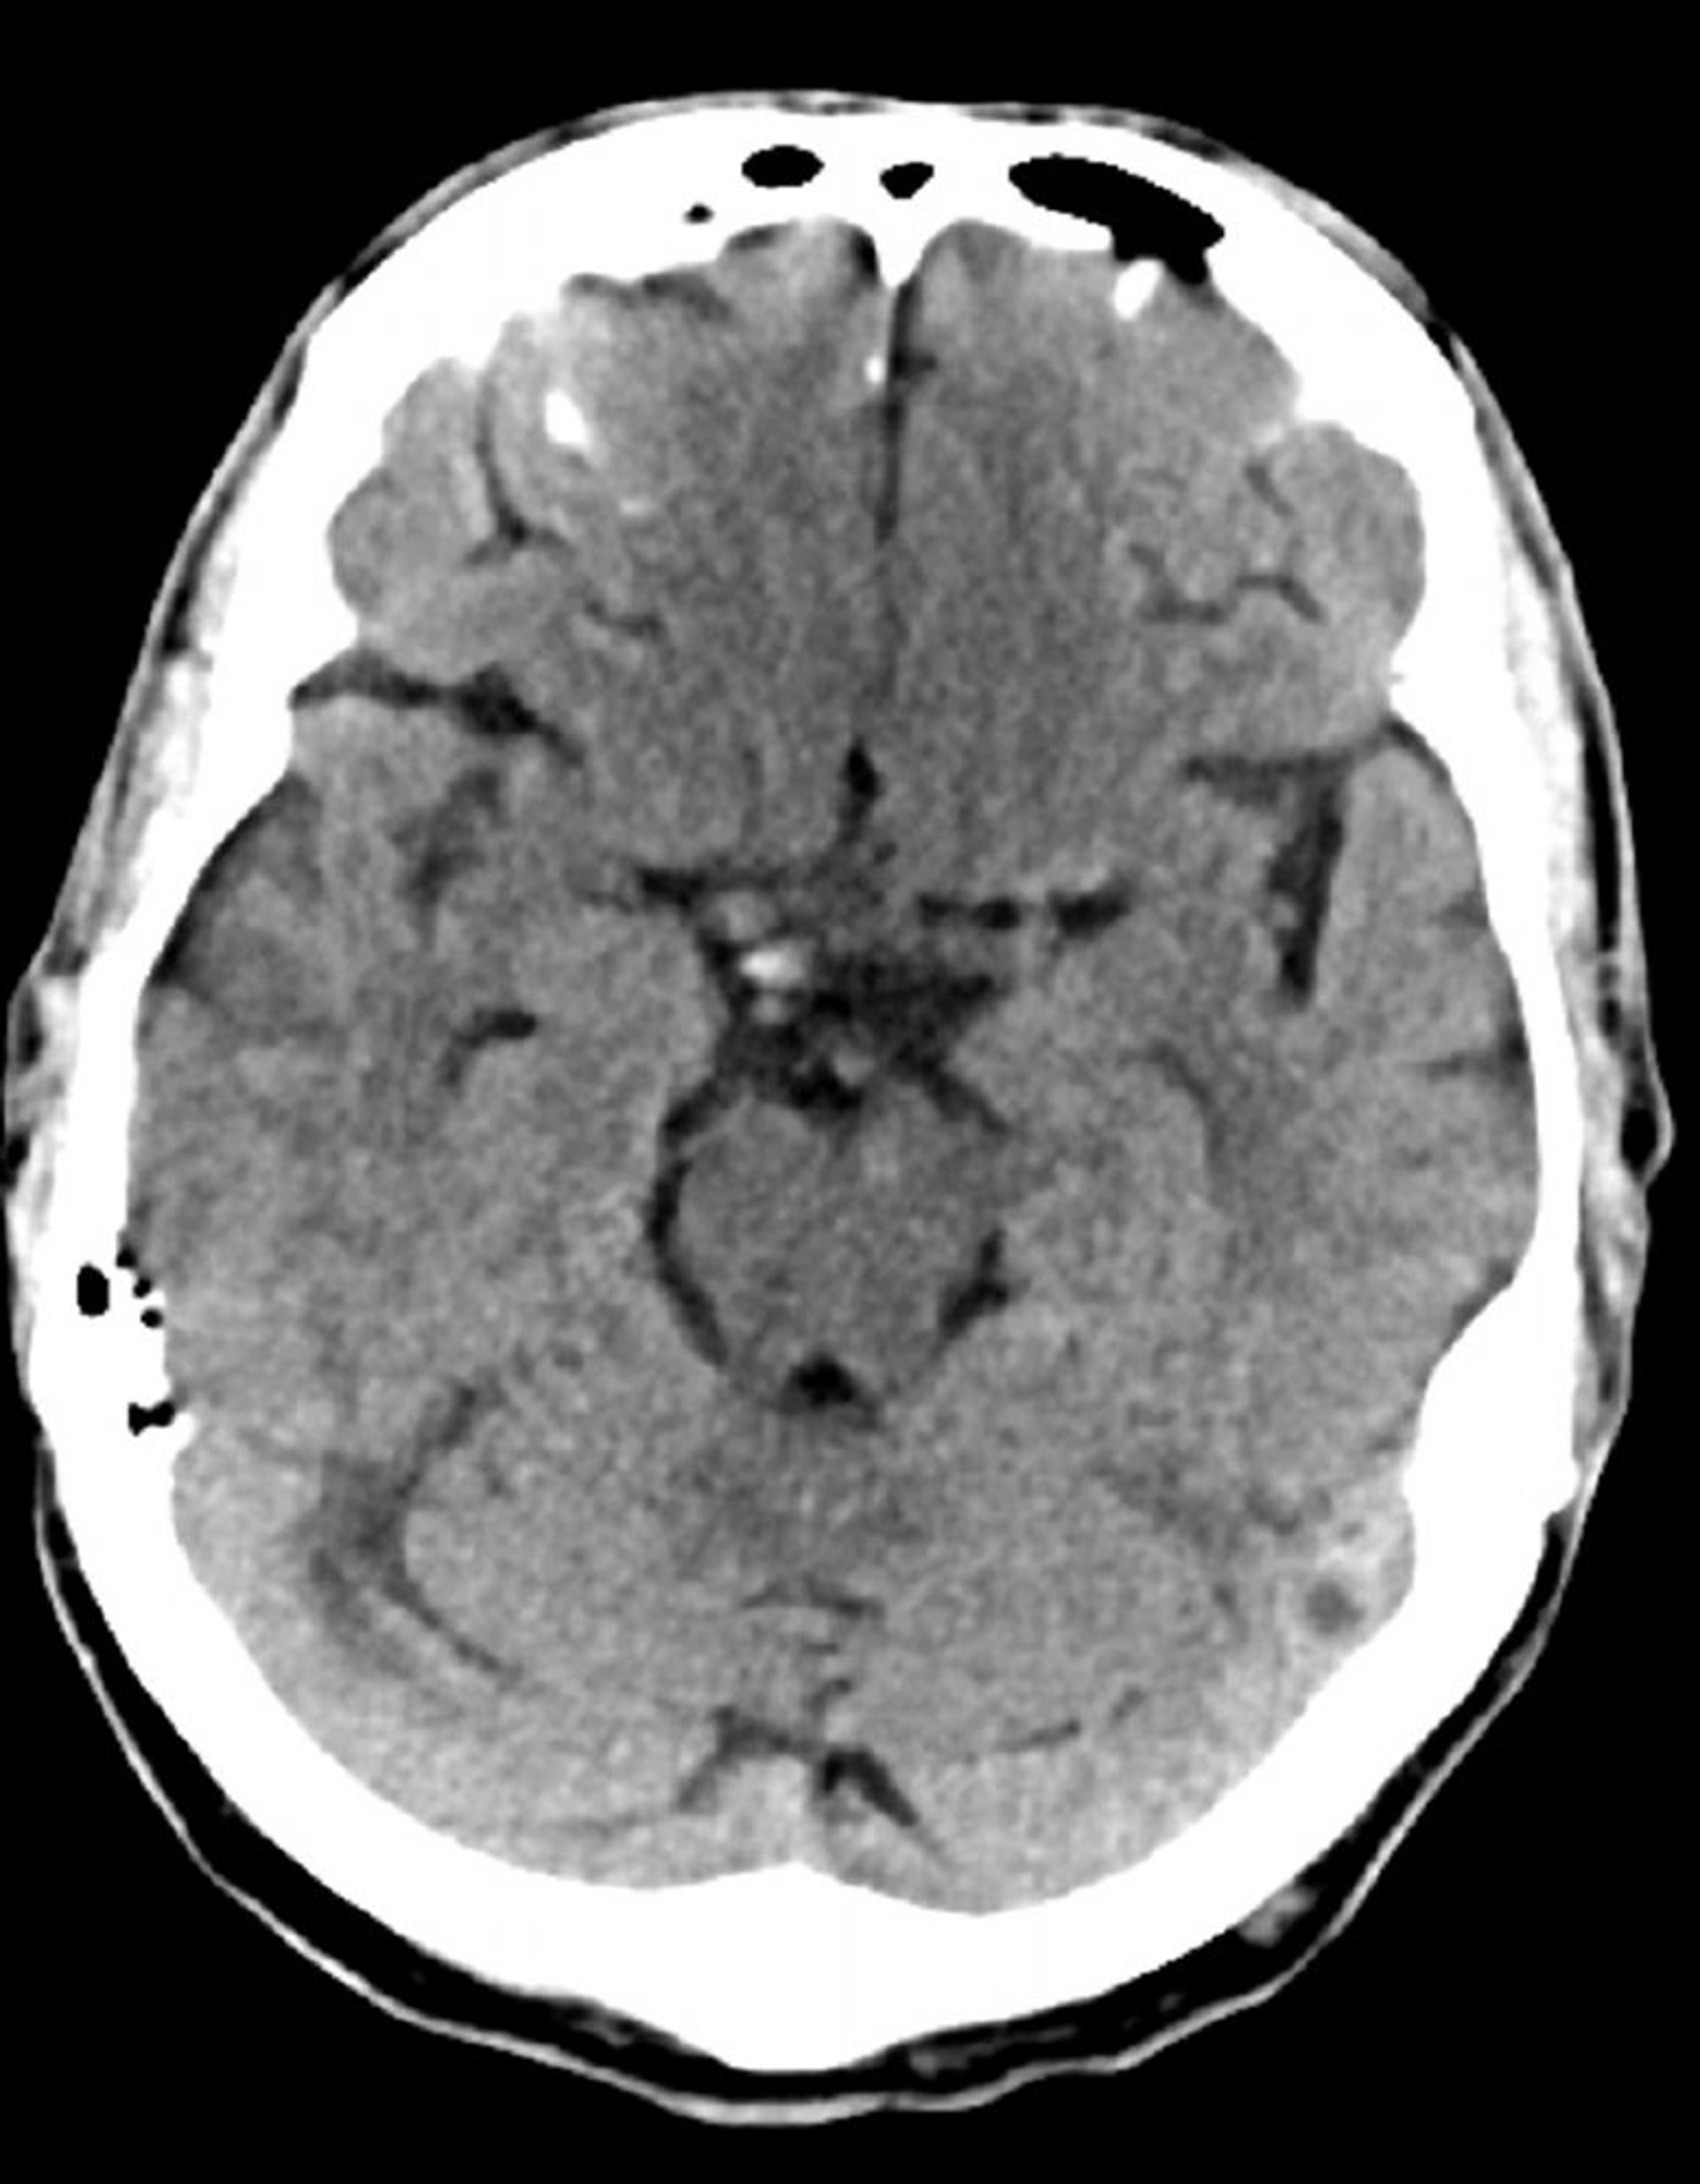

Tomografía computarizada craneal normal (adulto, 74 años)–diapositiva 7

Esta imagen es una tomografía computarizada craneal normal correspondiente a un adulto de 74 años. Cuando se compara con la tomografía computarizada craneal normal del adulto de 30 años de edad, se observa que los ventrículos y los sulcos son más grandes. Estos son hallazgos normales en este grupo de edad.